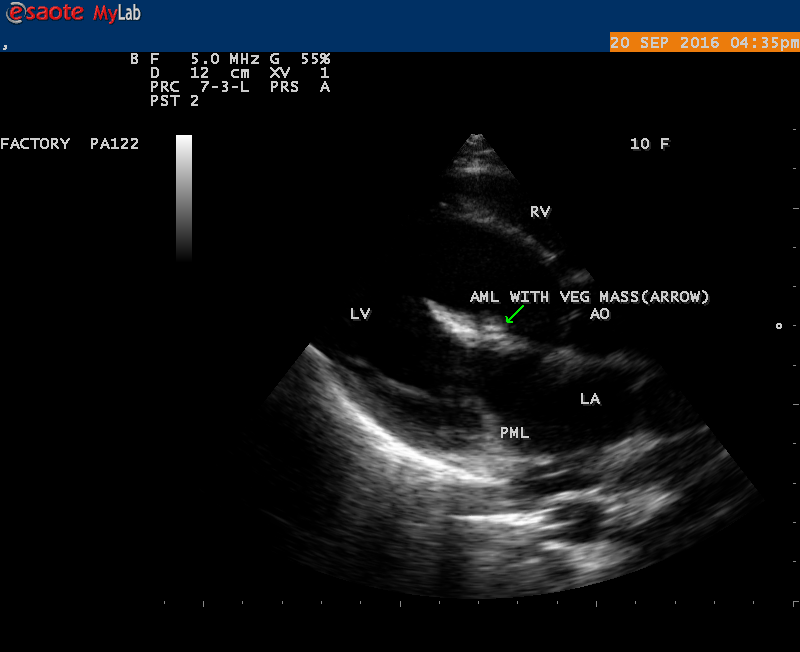

A 10 year female child was referred for echocardiographic evaluation with an apical systolic murmur. The child was having recurrent episodes of rheumatic fever (febrile illness with joint pains) at the age of 5-6 years and taken some treatment from the local medical practitioner, but she was not taken penicillin prophylaxis earlier. The child was remained afebrile for long period and no precipitating factors of infective endocarditis such as dental or genitourinary procedures in the past. General examination revealed normal growth and development, no cyanosis and clubbing and peripheral signs of infective endocarditis such s Osler’s nodes, Janeway lesions, Roths spots and splinter haemorrhages are not present and they are relatively rare in children. Physical examination revealed a grade 3/6 , blowing, high pitched, holosystolic murmur with a constant intensity and duration on dynamic auscultation and loudest at the apex with a radiation to left axilla and transmitted to the left infrascapular area and vertebral coloumn and it is due to the flow generating the murmur is directed posterolaterally within the left atrial cavity, suggesting the murmur of mitral regurgitation due to the rupture of chordae tendineae of anterior mitral leaflet. Blood culture revealed normal. Blood chemistry revealed the positive serum ASO titer, suggesting a recent streptococcal infection and other parameters are normal. X- ray chest reveled moderate cardiomegaly and ECG revealed a left ventricular volume overload pattern of eccentric hypertrophy due to LV dilatation as a result of severe mitral regurgitation and a normal rhythm. Transthoracic echocardiography revealed a giant vegetation ‘popcorn’ like in Figures 1,3 and 4 and ‘cucumber’ like in Figure 2, mainly attached to base and apical portion of anterior mitral leaflet as shown in Figure 31 and manifested in various size and shapes as shown in Figures 1 to 33. A flail anterior leaflet with a disorganized mitral regurgitation jet as shown in Figure 16 and 21 and the posterior leaflet is embedded with vegetation and resulting in ‘kissing forms’ as shown in Figures 13, 14 and 15 in echocardiography imaging. Tricuspid valve is also thickened and calcified as shown in Figure 2 in addition to thickened and calcified mitral leaflets, suggesting an underlying rheumatic etiology predisposing to the formation of vegetation. The child was given 1.2 million units of intramuscular benzathine penicillin injection as a therapeutic and initial prophylaxis dose for rheumatic fever and advised every 3 weeks for life long. Small doses of digoxin and diuretics are also prescribed and advised early surgery (mitral valve replacement) Transthoracic 2D images are as in Figures 1 to 33 are given below

The most common and direct evidence of infective endocarditis is the vegetation and it begins as a microscopic focus of infection and gradually grows into a conspicuous mass. It is typically an irregularly shaped, highly mobile, echogenic mass attached to the free edge of a valve leaflet ( most commonly at the coaptation line) and tends to develop on the ‘upstream’ side of the valve leaflets ( ie, the ventricular side of aortic valve and the atrial side of mitral and tricuspid valves. They may be seesile or pedunculated, but usually has an oscillating or fluttering motion, a typical feature of most vegetations. Vegetation move with the leaflet in a more chaotic (‘oscillating’) manner and it may prolapse through the valve into the LV (left ventricle) as it opens as shown in Figures 3, 4 and 16 and into LA (left atrium) as it closing (Figure 5 and 6) . The mass of vegetation is typically homogeneous with echogenicity similar to that of the myocardium. The infectious process often alter the valvular structure and function. Extensive involvement of the leaflet may result in chordal rupture, leading to severe regurgitation as shown in Figure 21 . Direct and typical signs of RMCT (ruptured mitral chordate tendineae) were chain-flail or whiplash-like changes and had an incidence of 86.7%, causing severe regurgitation and mitral chordal rupture is the leading cause of flail mitral leaflet[30]. A large vegetation may obstruct the valve orifice as shown in Figure 1 and 2 , sometimes termed as “obstructive-type bacterial endocarditis” and producing a functional valve stenosis ( Ping-Pong mitral stenosis [31]) similar to left atrial myxoma as shown in Figure 29.

The shape of vegetation varies in this child as ‘popcorn’ like (Figures 1,3 and 4 ), rod-shaped (Figure ), basket shaped (Figure 7 )[33-Figure 13.3], ‘baby in hand’ appearance (Figure 18), ‘cucumber shaped (Figure 2 ) and a ‘bunch of plantain’appearance (Figure 33 ), ring shaped (Figure 19 }, bileaflet structure (Figure 9 )with bileaflet MR jet as shown in Figure 10 . and kissing forms (Figure 13 - parasternal long axis view, Figure 14 - apical four chamber view and Figure 15 - short axis view)